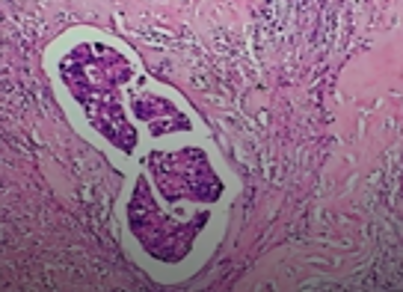

Ans to previous : (August 2025)

Tumour embolus in a lymphatic channel.